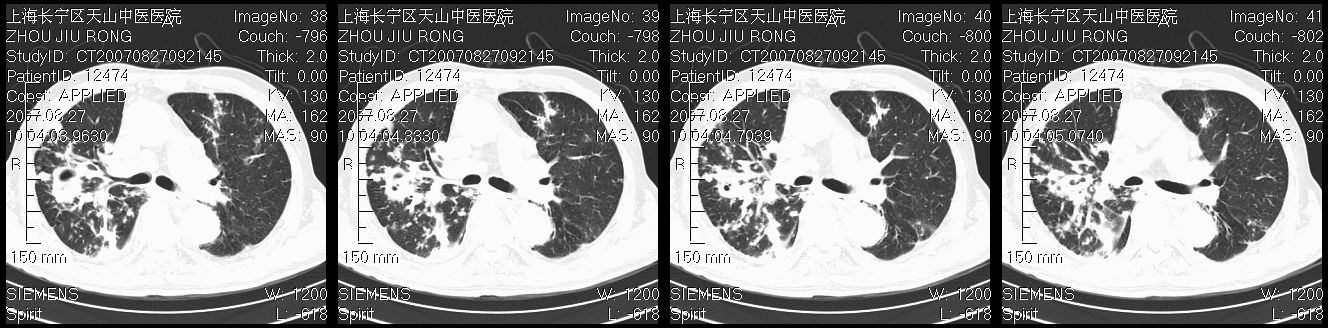

以下是引用zjzjr在2007-8-30 21:47:00的发言:[br]双肺弥漫性结节状、斑片状影,部分形成空洞,病灶以双肺上叶为著(符合结核发病部位),纵隔内见肿大淋巴结影。支持双肺继发性结核伴右上肺空洞形成。

以下是引用zjzjr在2007-8-30 21:47:00的发言:[br]双肺弥漫性结节状、斑片状影,部分形成空洞,病灶以双肺上叶为著(符合结核发病部位),纵隔内见肿大淋巴结影。支持双肺继发性结核伴右上肺空洞形成。

以下是引用gaoshengjiang在2007-8-31 10:24:00的发言:[br]双肺弥漫性斑片状影及多发空洞影,其间夹杂多量条索状影,胸膜肥厚、粘连并有结节状改变,纵隔多枚淋巴结肿大,考虑1双肺继发型肺结核合并感染?2韦格氏肉芽肿?[br] 支持!

以下是引用zjzjr在2007-8-30 21:47:00的发言:[br]双肺弥漫性结节状、斑片状影,部分形成空洞,病灶以双肺上叶为著(符合结核发病部位),纵隔内见肿大淋巴结影。支持双肺继发性结核伴右上肺空洞形成。

以下是引用zjzjr在2007-8-30 21:47:00的发言:[br]双肺弥漫性结节状、斑片状影,部分形成空洞,病灶以双肺上叶为著(符合结核发病部位),纵隔内见肿大淋巴结影。支持双肺继发性结核伴右上肺空洞形成。

以下是引用zjzjr在2007-8-30 21:47:00的发言:[br]双肺弥漫性结节状、斑片状影,部分形成空洞,病灶以双肺上叶为著(符合结核发病部位),纵隔内见肿大淋巴结影。支持双肺继发性结核伴右上肺空洞形成。